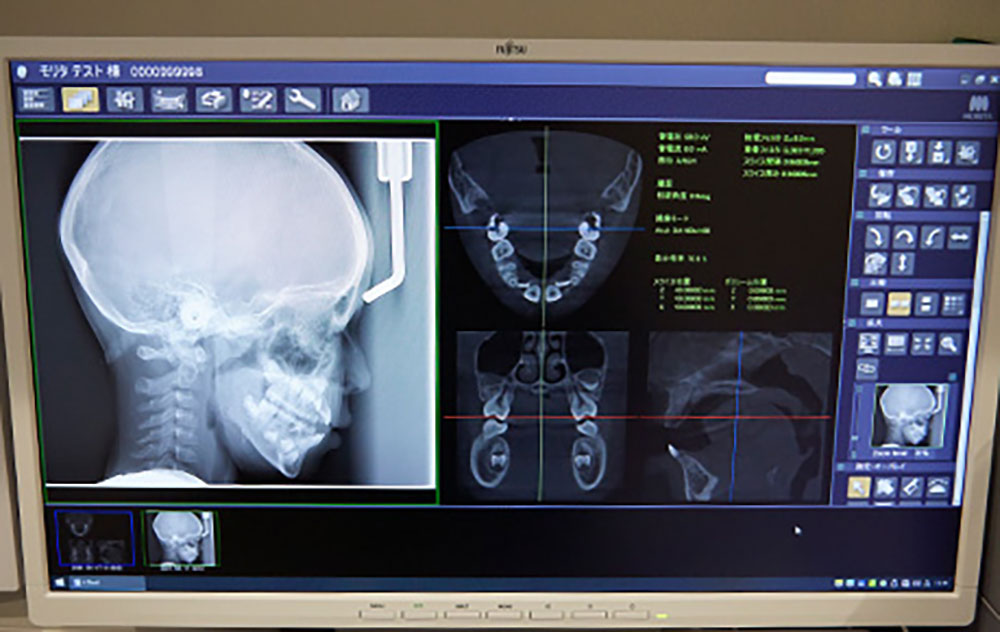

頭部X線規格写真を用いた咬合分析で、精緻な矯正治療を実践

矯正歯科用の特別なレントゲン。頭を基準にして歯の傾き、上下の顎骨の位置関係、歯列の形態や位置を撮影し、咬合状態を精緻に確認することで、精度の良い矯正治療を実現します。